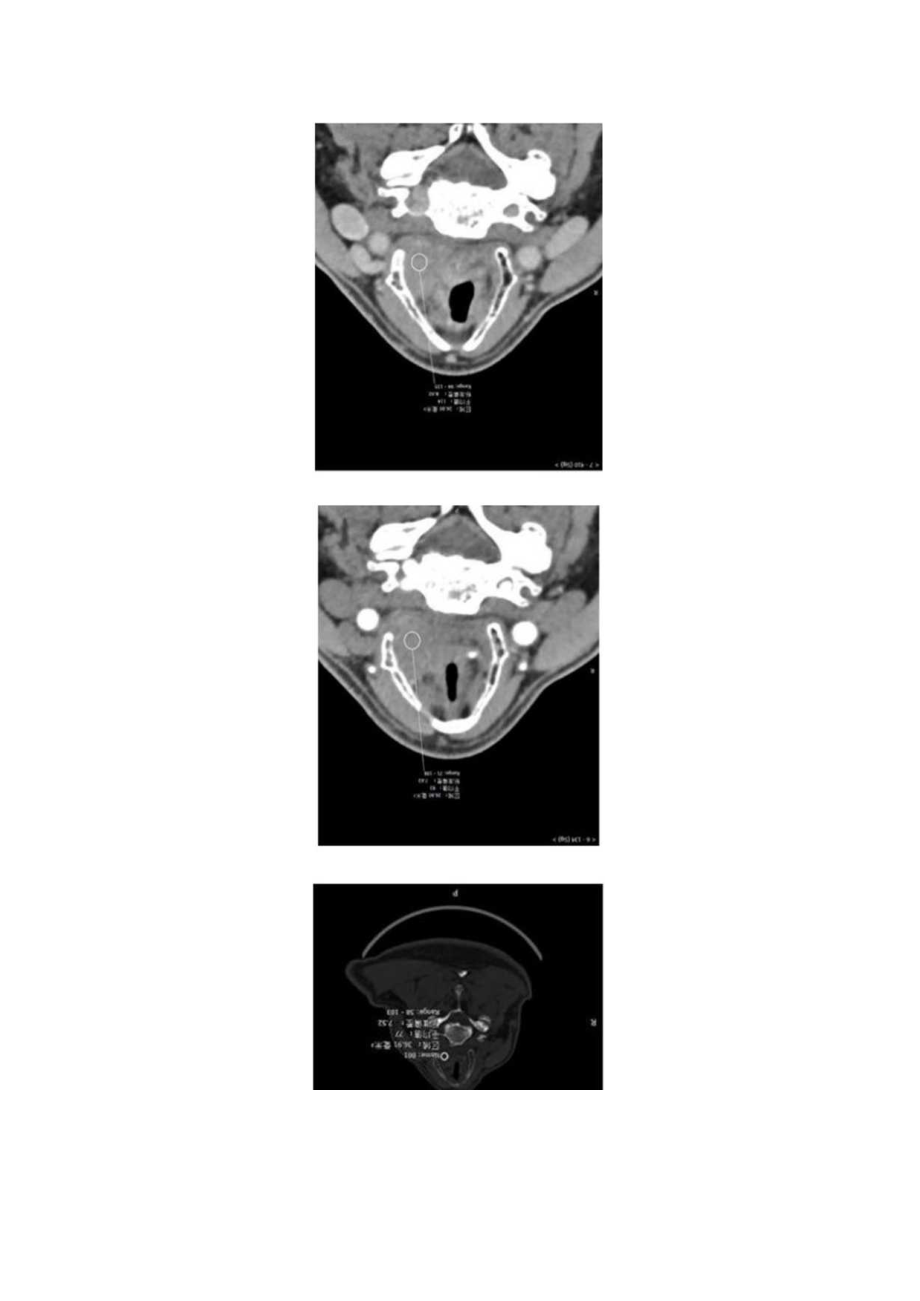

喉部肿物病例分析专题报告病例报告患者,男,64岁,咽部异物3月。患者3月前无明显诱因出现咽部异物感,就诊我院门诊后行抗炎治疗症状缓解2天后症状反复。后反复出现,偶有针刺感,后行纤维喉镜检查后发现会厌根部肿物。患者自发病以来无吞咽及呼吸困难,无饮水呛咳。影像图片讨论评论:声门上层面喉左后壁增厚,呈软组织密度肿块影,边界不清,左侧杓状软骨大部分显示不清,左侧甲状软骨边缘毛糙,增强扫描呈渐进性轻度强化。诊断(会厌囊肿)符合会厌囊肿病例小结会厌囊肿是耳鼻咽喉科的常见疾病,约占喉部囊肿的20%o会厌囊肿多系因粘膜粘液腺管口堵塞所引起的粘液潴留囊肿。会厌囊肿的病变局限,形态规则无分叶,为口底小腺体阻塞后的潴留囊肿,位于上颈部会厌前间隙。MR1.影像为囊性长T1.长T2信号肿块,边界清晰,其内信号均匀,可见咽喉腔受压变窄,CT影像为囊性薄壁低密度肿块,边界清晰,密度均匀,相应水平口咽腔受压变窄。